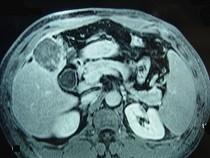

问题 男性,60岁,右上腹胀不适,右肝区叩击痛,影像检查如图,最可能的诊断是()

选项 A.肝硬化 B.肝硬化、外生性肝癌 C.肝硬化、腹腔间质瘤 D.肝硬化、膈下脓肿 E.肝硬化、结节性增生

答案 B